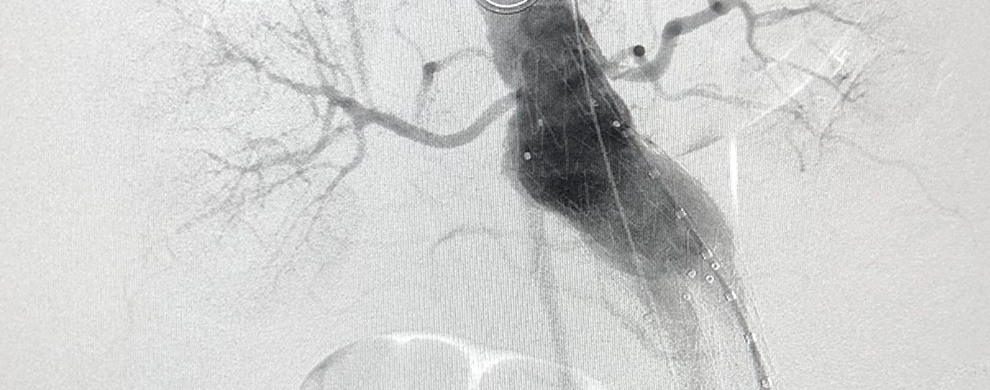

Increasing Surveillance of EVAR Patients To Improve Long-term Outcomes